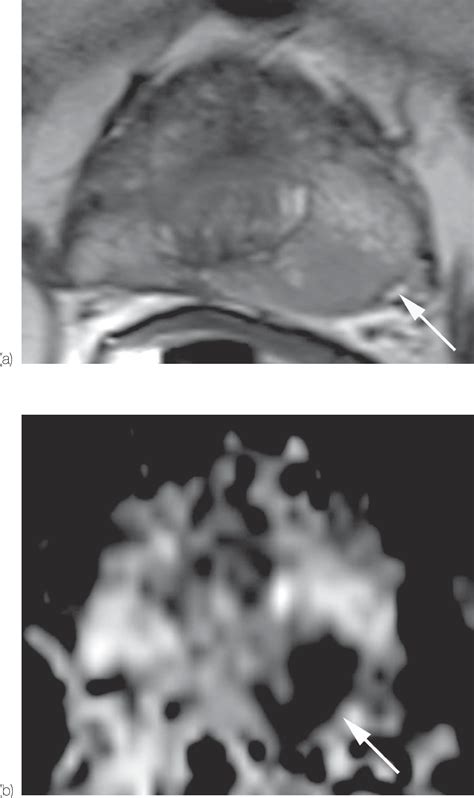

When a patient is assigned a Pi Rads 4 score, it means that there is a well-defined lesion on the MRI that exhibits characteristics highly suggestive of a potentially aggressive tumor. Specifically, for peripheral zone lesions, this means a focal, low-signal intensity lesion on T2-weighted imaging and marked diffusion restriction on Diffusion-Weighted Imaging (DWI). For transition zone lesions, it refers to a lenticular or non-circumscribed, encapsulated, moderately hypointense lesion.